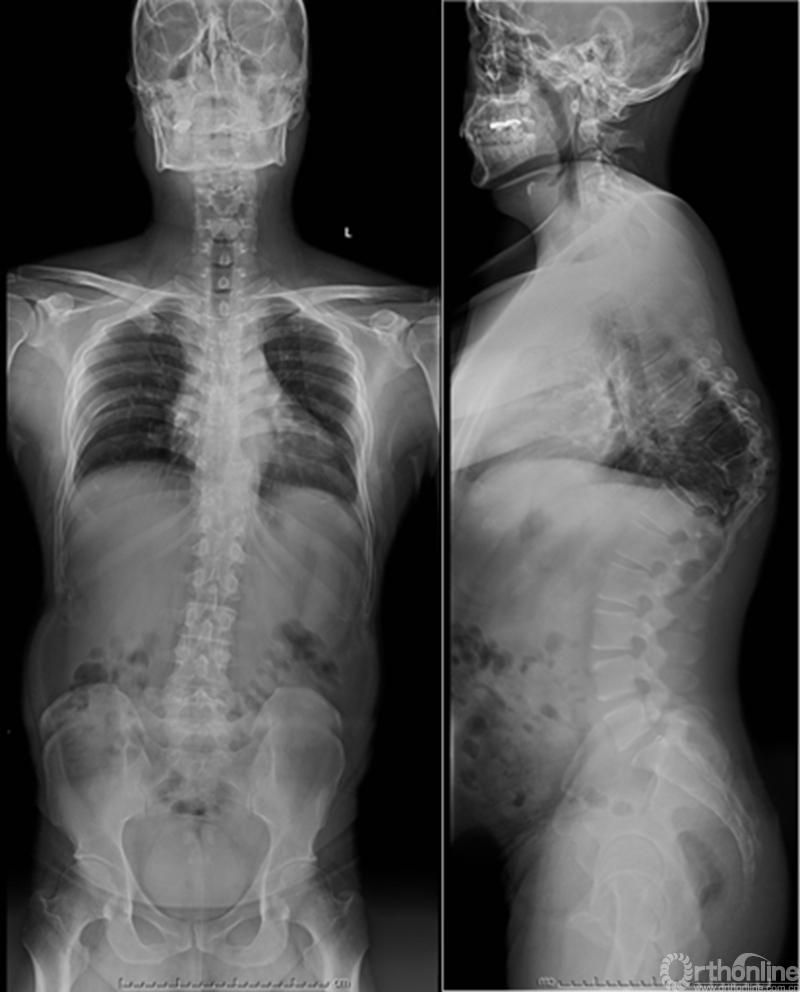

患者资料

门诊结束后,丁文元教授立刻带领团队成员开始查阅大量相关文献,为大帅的手术进行充足的准备和周密的计划。幸运的是手术很顺利,术后复查各项指标恢复良好,大帅的头也抬起了来了,脸上洋溢着久违的笑容,这给了医生和患者家庭极大的信心。

患者术前资料

患者术后资料